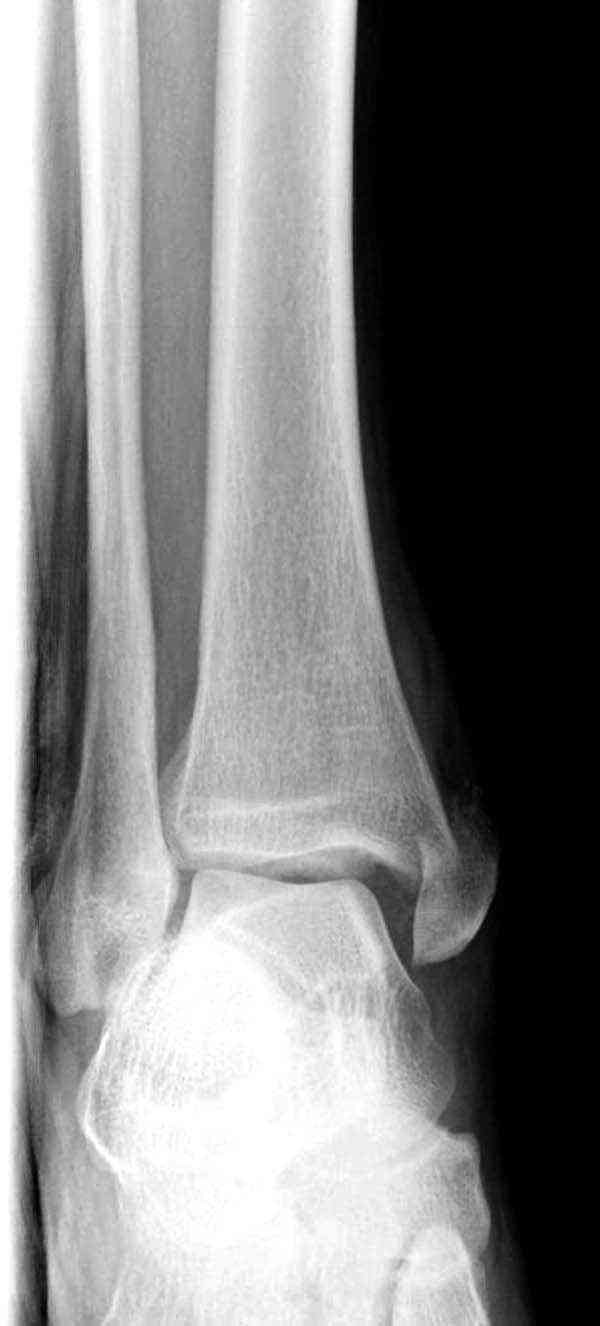

Случай прошлого года:пациентка-молодая ,крупная женщина ,30лет.Травма в начале апреля 2009г-пронационный перелом лодыжек с подвывихом стопы.Ко мне обратилась через 35 дней,прооперирована 22.05.2009г.Внутренняя лодыжка фиксирована по Веберу,наружная реконструктивной пластиной с наложением болта-стяжки.Иммобилизация "сапожок" в течении месяца,затем пригипсовано "стремя".Гипс снят 10.07.2009г

Достаточно быстрое восстановление функции.В октябре 2009г-почувствовала боль,в области рубца над гайкой открылся свищ.На Р-граммах-консолидация переломов и смещение гайки по стяжке.10.11.2009г-конструкции удалены,санация,заживление ран.В настоящее время пациентку ничего не беспокоит.На операции-раскручивание гайки-болталась на конце стяжки.Вопросы:какой механизм раскручивания и что я неправильно сделал?Свои версии:1)в области синдесмоза успела образоваться рубцовая ткань,которая при движении в суставе"пружинила",поскольку голеностопный сустав является спиральным, то и биомеханика подобна кривошипному механизму.2)Реконструктивная пластина не "реконструировалась" по форме лодыжки.Наложил,как есть.То есть подпружинивала сама пластина.Ну,это мои догадки.Что нужно,чтобы избегать впредь таких,пусть и не "страшных"осложнений:Рассверливать через лодыжку область синдесмоза?Ставить шайбу-гровер?Тщательно моделировать пластину?Прилагаю сравнительные снимки-сразу после операции и перед удалением конструкции.

Визуально никаких вопросов по репозиции не было.Да и на основании чего сомнения,что наружная лодыжка не полностью репонирована или прорезалась проволка ???Я не вижу...Снимок после репозиции справа.

Раз ,есть желание посмотреть другую проекцию выкладываю-ну лучшего качества нет...

Нет первичных снимков, перелом очень низкий и под большим сомнением диагноз разрыва синдесмоза. Медиальная сторона отрепонирована на "хорошо" и, по-видимому, прорезание проволоки произошло во время операции. Без снимков трудно судить о высоте малоберцовой, а лодыжка находится в варусе. Лагирование получилось, но возле тонких шурупов передне-задний шуруп выглядит немного тяжеловато.